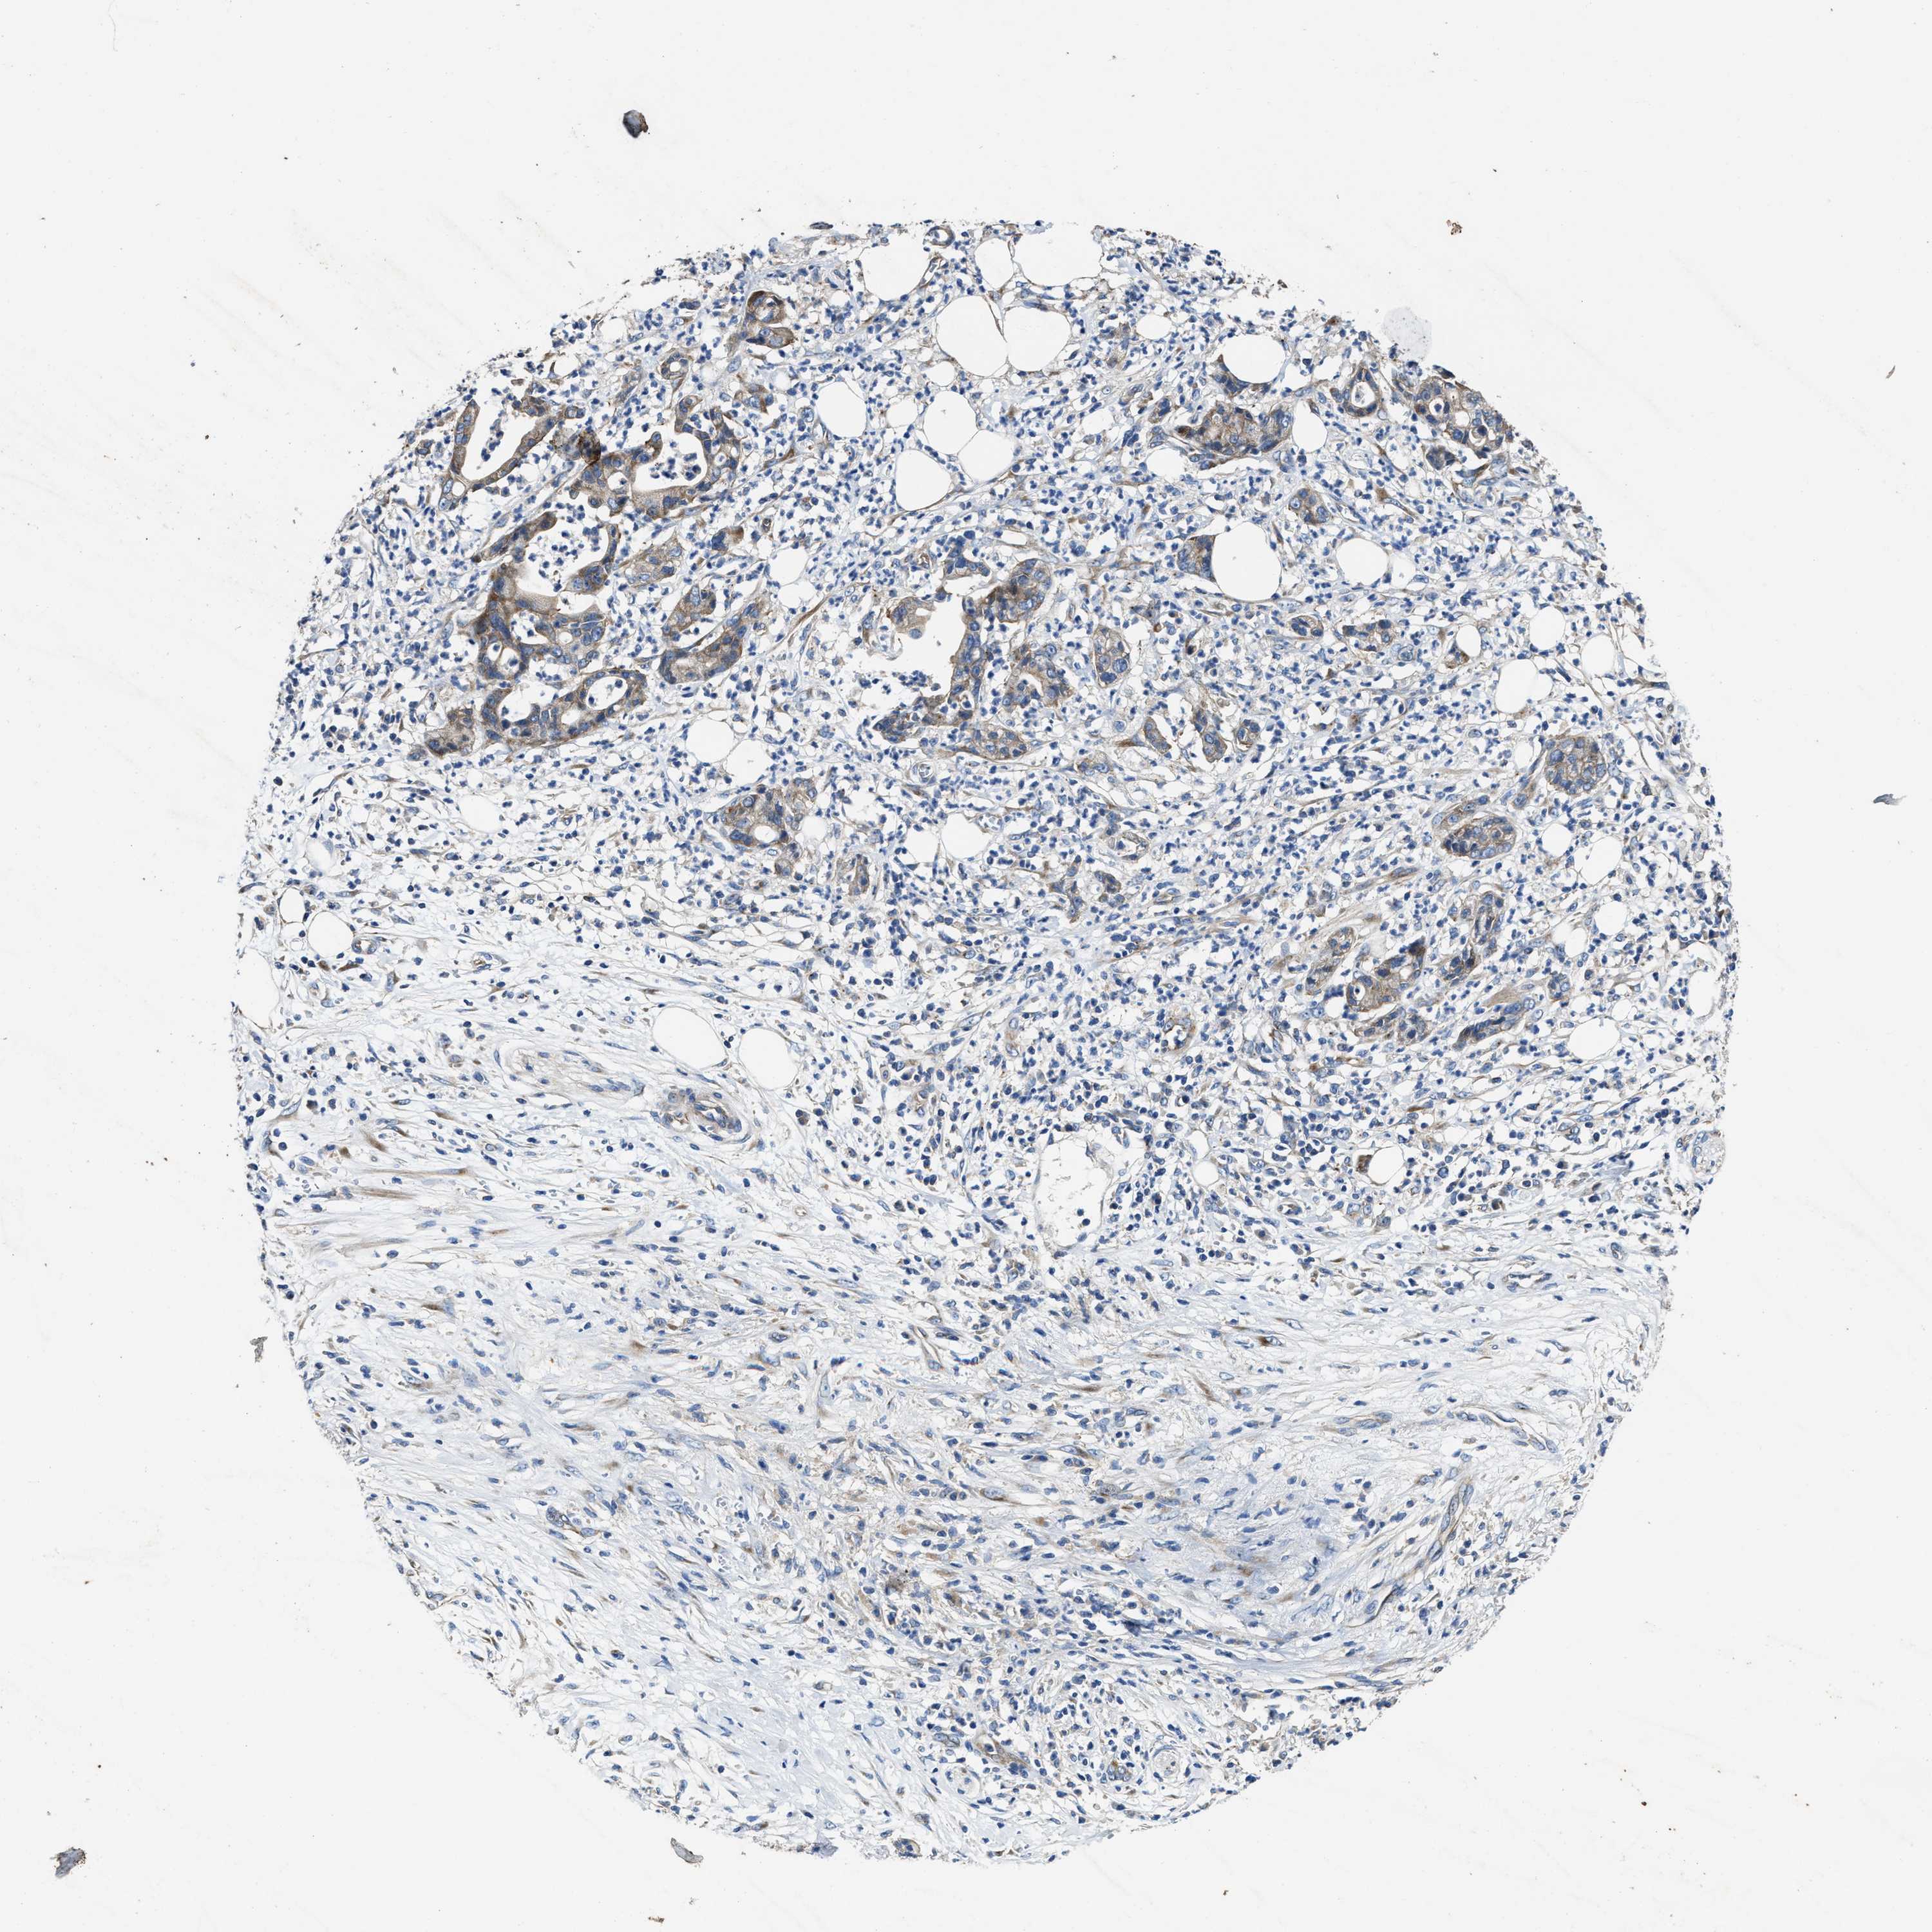

PANCREATIC CANCER - Protein expressioni

A mouse-over function shows sample information and annotation data. Click on an image to view it in a full screen mode. Samples can be filtered based on level of antibody staining by selecting one or several of the following categories: high, medium, low and not detected. The assay and annotation is described here.

Note that samples used for immunohistochemistry by the Human Protein Atlas do not correspond to samples in the TCGA dataset.

Antibody stainingi

Antibody staining in the annotated cell types in the current human tissue is reported as not detected, low, medium, or high, based on conventional immunohistochemistry profiling in selected tissues. This score is based on the combination of the staining intensity and fraction of stained cells.

Each image is clickable and will lead to virtual microscopy that enables deeper exploration of all samples and also displays staining intensity scores, fraction scores and subcellular localization as well as patient and tissue information for each sample.

Antibody HPA021248

Staining

High

Medium

Low

Not detected

Intensity

Strong

Moderate

Weak

Negative

Quantity

>75%

75%-25%

<25%

None

Location

Nuclear

Cytoplasmic/membranous

Cytoplasmic/membranous,nuclear

Adenocarcinoma, NOS